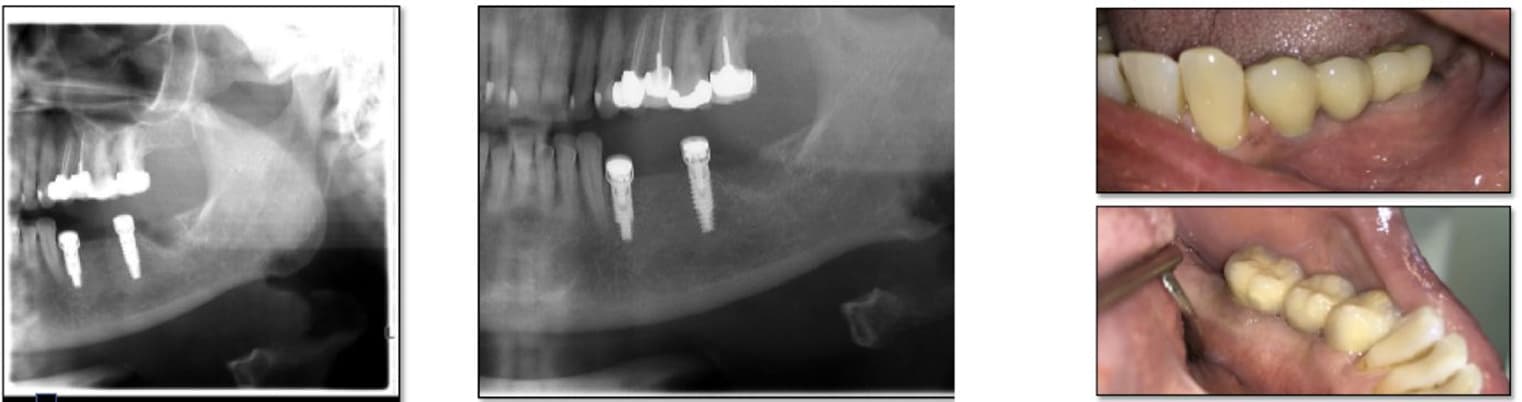

This case, performed by Prof. Alberto Monje, involved a patient diagnosed with inflammatory environment, presenting with advanced bone loss and bleeding on probing. The treatment followed a surgical regenerative protocol combining mechanical decontamination and biological stimulation using the MAGDENT Miniaturized Electromagnetic Device (MED). The procedure included implantoplasty, thorough surface debridement and decontamination, and guided bone regeneration (GBR) with a particulate bone graft and collagen membrane to restore the lost peri-implant bone structure. Immediately after the regenerative procedure, the MED healing abutment was connected to the implant and left in place for three weeks, delivering continuous pulsed electromagnetic field (PEMF) stimulation to promote cellular activation, angiogenesis, and bone remodeling at the defect site.

After soft tissue stabilization, the prosthesis was reinstalled, and long-term follow-up at 11 months demonstrated excellent clinical and radiographic outcomes. The treated site exhibited complete mucosal healing, absence of inflammation or pocketing, and stable bone regeneration with clear re-establishment of crestal bone levels around the implant. Radiographs confirmed maintenance of the regenerated bone volume and implant stability, while clinical evaluation showed healthy peri-implant tissues with ideal color, tone, and contour.

• This case highlights the effectiveness of the surgical inflammatory environment management protocol integrating PEMF technology, showing how the MED device can enhance bone regeneration and accelerate healing when combined with conventional regenerative techniques such as implantoplasty and GBR. The synergy between surgical decontamination and electromagnetic stimulation supports a predictable, biologically driven regeneration in peri-implant defects, offering a viable alternative to more invasive resection procedures.

Inflammatory environment Surgical Regeneration (Prof. Alberto Monje, DDS, MS, PhD) This clinical case, documented by Prof. Alberto Monje and published in Periodontology 2000 (“Emerging locally delivered antimicrobial and immunomodulatory approaches for the prevention/treatment of peri-implant diseases,” Monje et al., DOI: 10.1111/prd.12638), presents a surgically managed inflammatory environment defect with the integration of Magdent’s Miniaturized Electromagnetic Device (MED) as an adjunctive regenerative tool. The patient was diagnosed with inflammatory environment accompanied by inflammation and progressive bone loss (A–B). The disease had persisted despite prior nonsurgical therapy (C). During the surgical phase, granulation tissue was meticulously removed by curettage (D), and implantoplasty was performed on the exposed implant surface to smooth irregularities and reduce bacterial adhesion (E). Subsequent electrolytic decontamination of the intrabony area was performed using the GalvoSurge system (F), ensuring optimal surface disinfection prior to regeneration. Following decontamination, a guided bone regeneration (GBR) procedure was performed using a particulate bone graft, after which the Magdent PEMF healing abutment was immediately connected to the implant (G). The MED device delivered pulsed electromagnetic field (PEMF) stimulation over a period of three weeks, enhancing cellular activity, vascularization, and bone remodeling during the early healing phase.

At 9 months, clinical evaluation revealed complete soft tissue healing, resolution of inflammation, and reestablishment of mucosal seal (H). At 1-year follow-up, radiographs confirmed substantial bone regeneration and defect fill with stable crestal bone levels and restored implant function (I).

• This case underscores the clinical efficacy of combining regenerative surgery, decontamination, and electromagnetic stimulation. The synergy between implantoplasty, electrolytic cleaning, and Magdent PEMF therapy demonstrates a predictable, minimally invasive, and biologically enhanced approach to inflammatory environment management, providing both functional and histological regeneration outcomes in previously compromised implant sites.